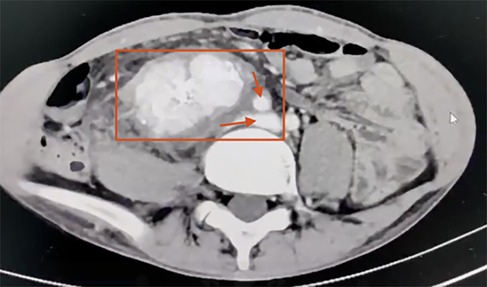

Laboratory tests revealed leukocytosis with a white blood cell count of 12.13 × 109/L (reference range: 3.5–9.5 × 109/L, ↑), neutrophilia with neutrophils accounting for 92.4% (reference range: 40%–75%, ↑), hemoglobin 153 g/L (reference range: 130–175 g/L, normal), and platelet count 368 × 109/L (reference range: 125–350 × 109/L, ↑). Serum biochemistry demonstrated decreased prealbumin at 160 mg/L (reference range: 200–400 mg/L, ↓), decreased albumin at 32.9 g/L (reference range: 40–55 g/L, ↓), and hypokalemia with potassium at 3.09 mmol/L (reference range: 3.5–5.3 mmol/L, ↓). Tumor marker analysis revealed an elevated carcinoembryonic antigen (CEA) level of 7.170 ng/ml (reference range: 0–5 ng/ml, ↑). Coagulation studies showed a mildly prolonged prothrombin time–international normalized ratio (PT-INR) of 1.27 (reference range: 0.8–1.2, ↑) and elevated plasma fibrinogen at 5.70 g/L (reference range: 2–4 g/L, ↑). Contrast-enhanced CT demonstrated a 17 × 10 × 4 cm retroperitoneal mass encasing the right iliac vessels and inferior vena cava (Figure 2) consistent with liposarcoma.

Figure 2. Contrast-enhanced abdominal CT scan demonstrating a malignant retroperitoneal mass (17 × 10 × 4 cm) encasing the right iliac vessels and inferior vena cava (the red box highlights a retroperitoneal malignant mass. The superior arrow indicates encasement of the right iliac vessels, while the inferior arrow indicates encasement of the inferior vena cava).